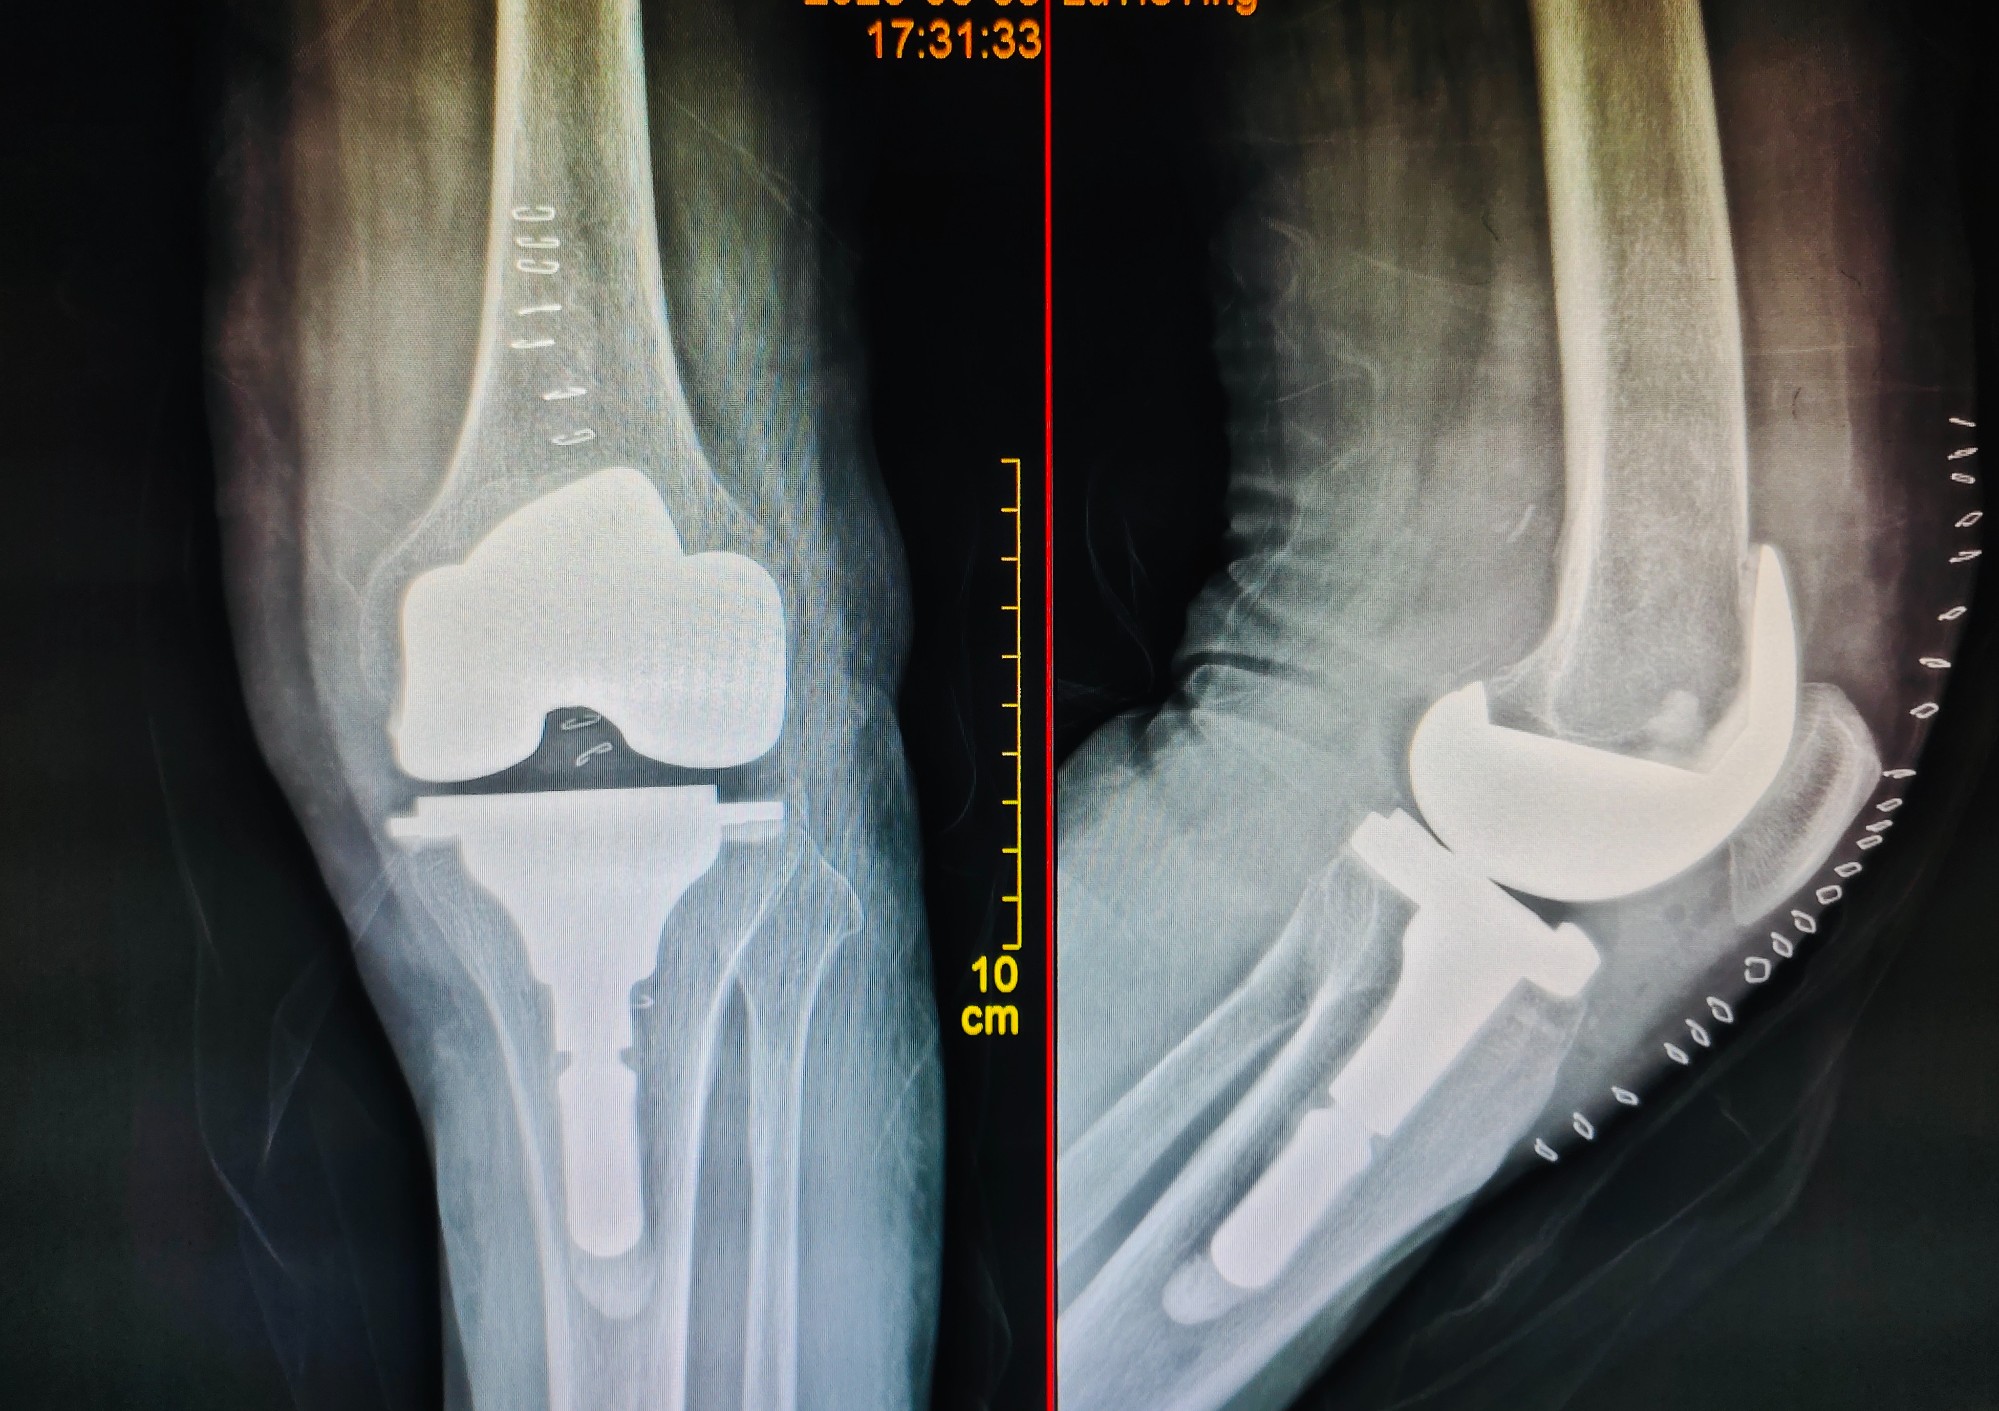

2、关节专科:关节内骨折,脱位复位内固定术;半月板损伤,关节韧带损伤行关节镜微创修复及关节功能重建术;膝关节表面置换术,人工股骨头置换术,全髋关节置换术,假体周围骨折重建及返修术,股骨头缺血坏死血管介入治疗,钻孔减压及异体骨植入术,带血管肌骨瓣植入术等。

膝关节置换术